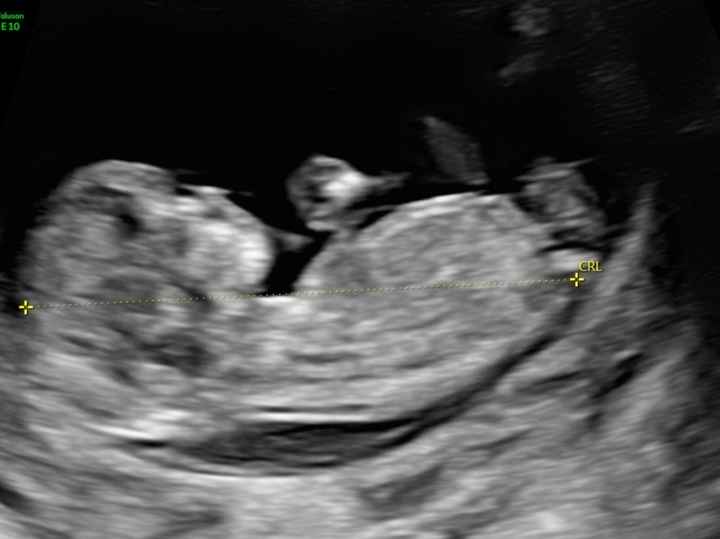

Mancano ancora tantissime settimane alla morfologica, che avrò il 15 Luglio, mi ritrovo spesso a fantasticare se sarà Filippo o Lucrezia, io mi sento maschio ma non si sa mai.

Mi affido a voi esperte di Nub Theory, cosa dite maschio o femmina??